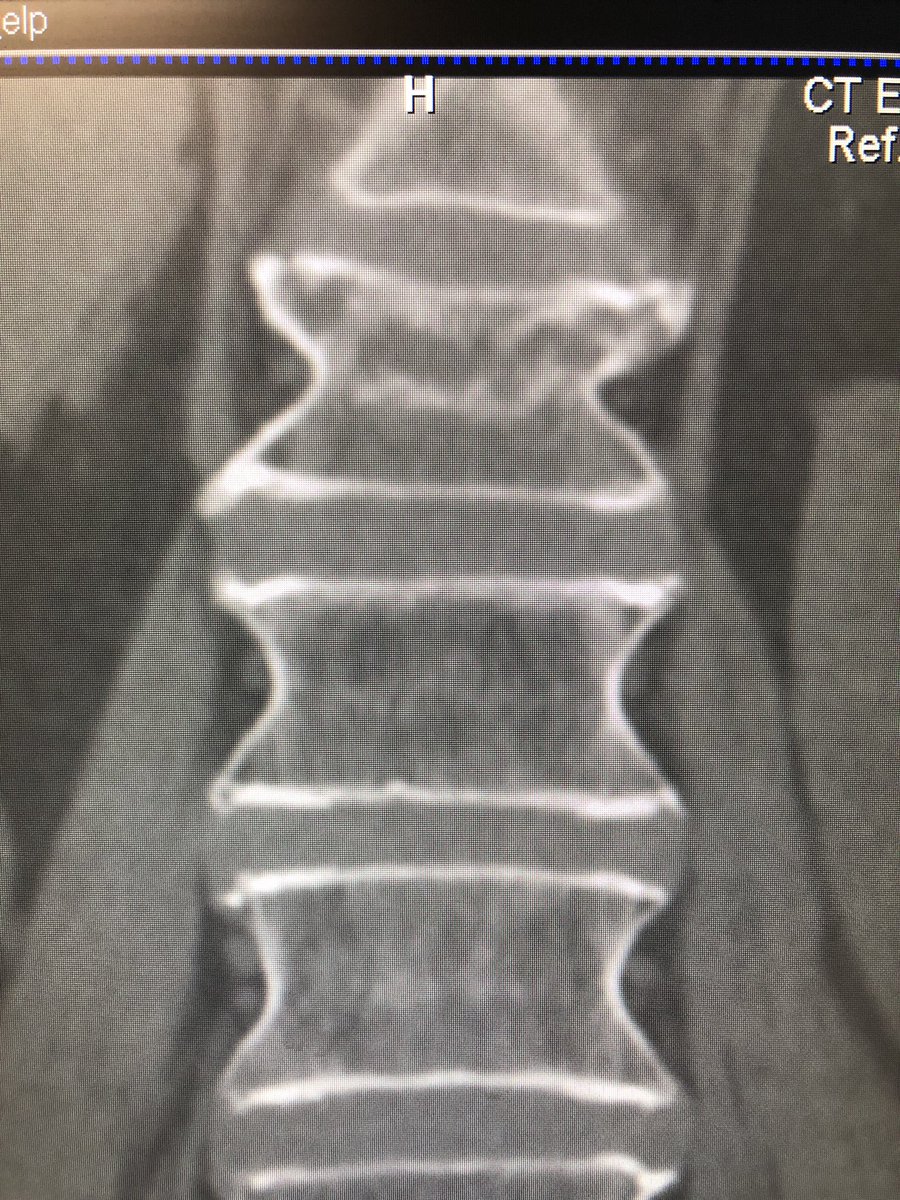

L1 vertebral Fx with nice endplate reduction and immediate pain relief.

@stryker_spine#miips#irads#SpineRad pic.twitter.com/UFXAvrI2An – mjesto: Froedtert Hospital